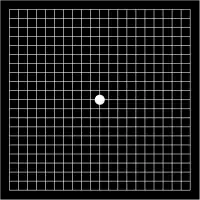

The original Amsler grid was black and white. A color version with a blue and yellow grid is more sensitive and can be used to test for a wide variety of visual pathway abnormalities, including those associated with the retina, the optic nerve, and the pituitary gland.

Chart 1 is the basic version, which is the most familiar and widely used chart among all the charts. In this chart the grid consists of 0.5 cm squares (each for 1° visual field), which totally measures 10 cm X 10 cm size. Most commonly grid is in white color with black background.[3] Grid with black lines in white background is also available (see infobox picture).